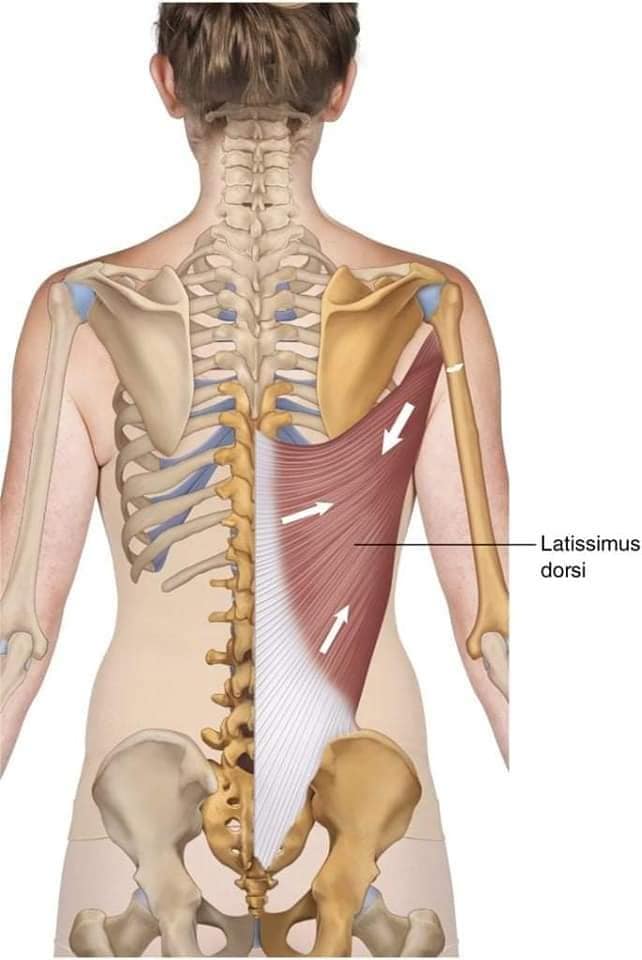

М'язи, що ведуть лопатку до хребта: Широкий м'яз спини: великий м'яз, що розташований в нижній частині спини. Він відповідає за рухи плечей і лопаток, а також за розширення верхньої частини тулуба.